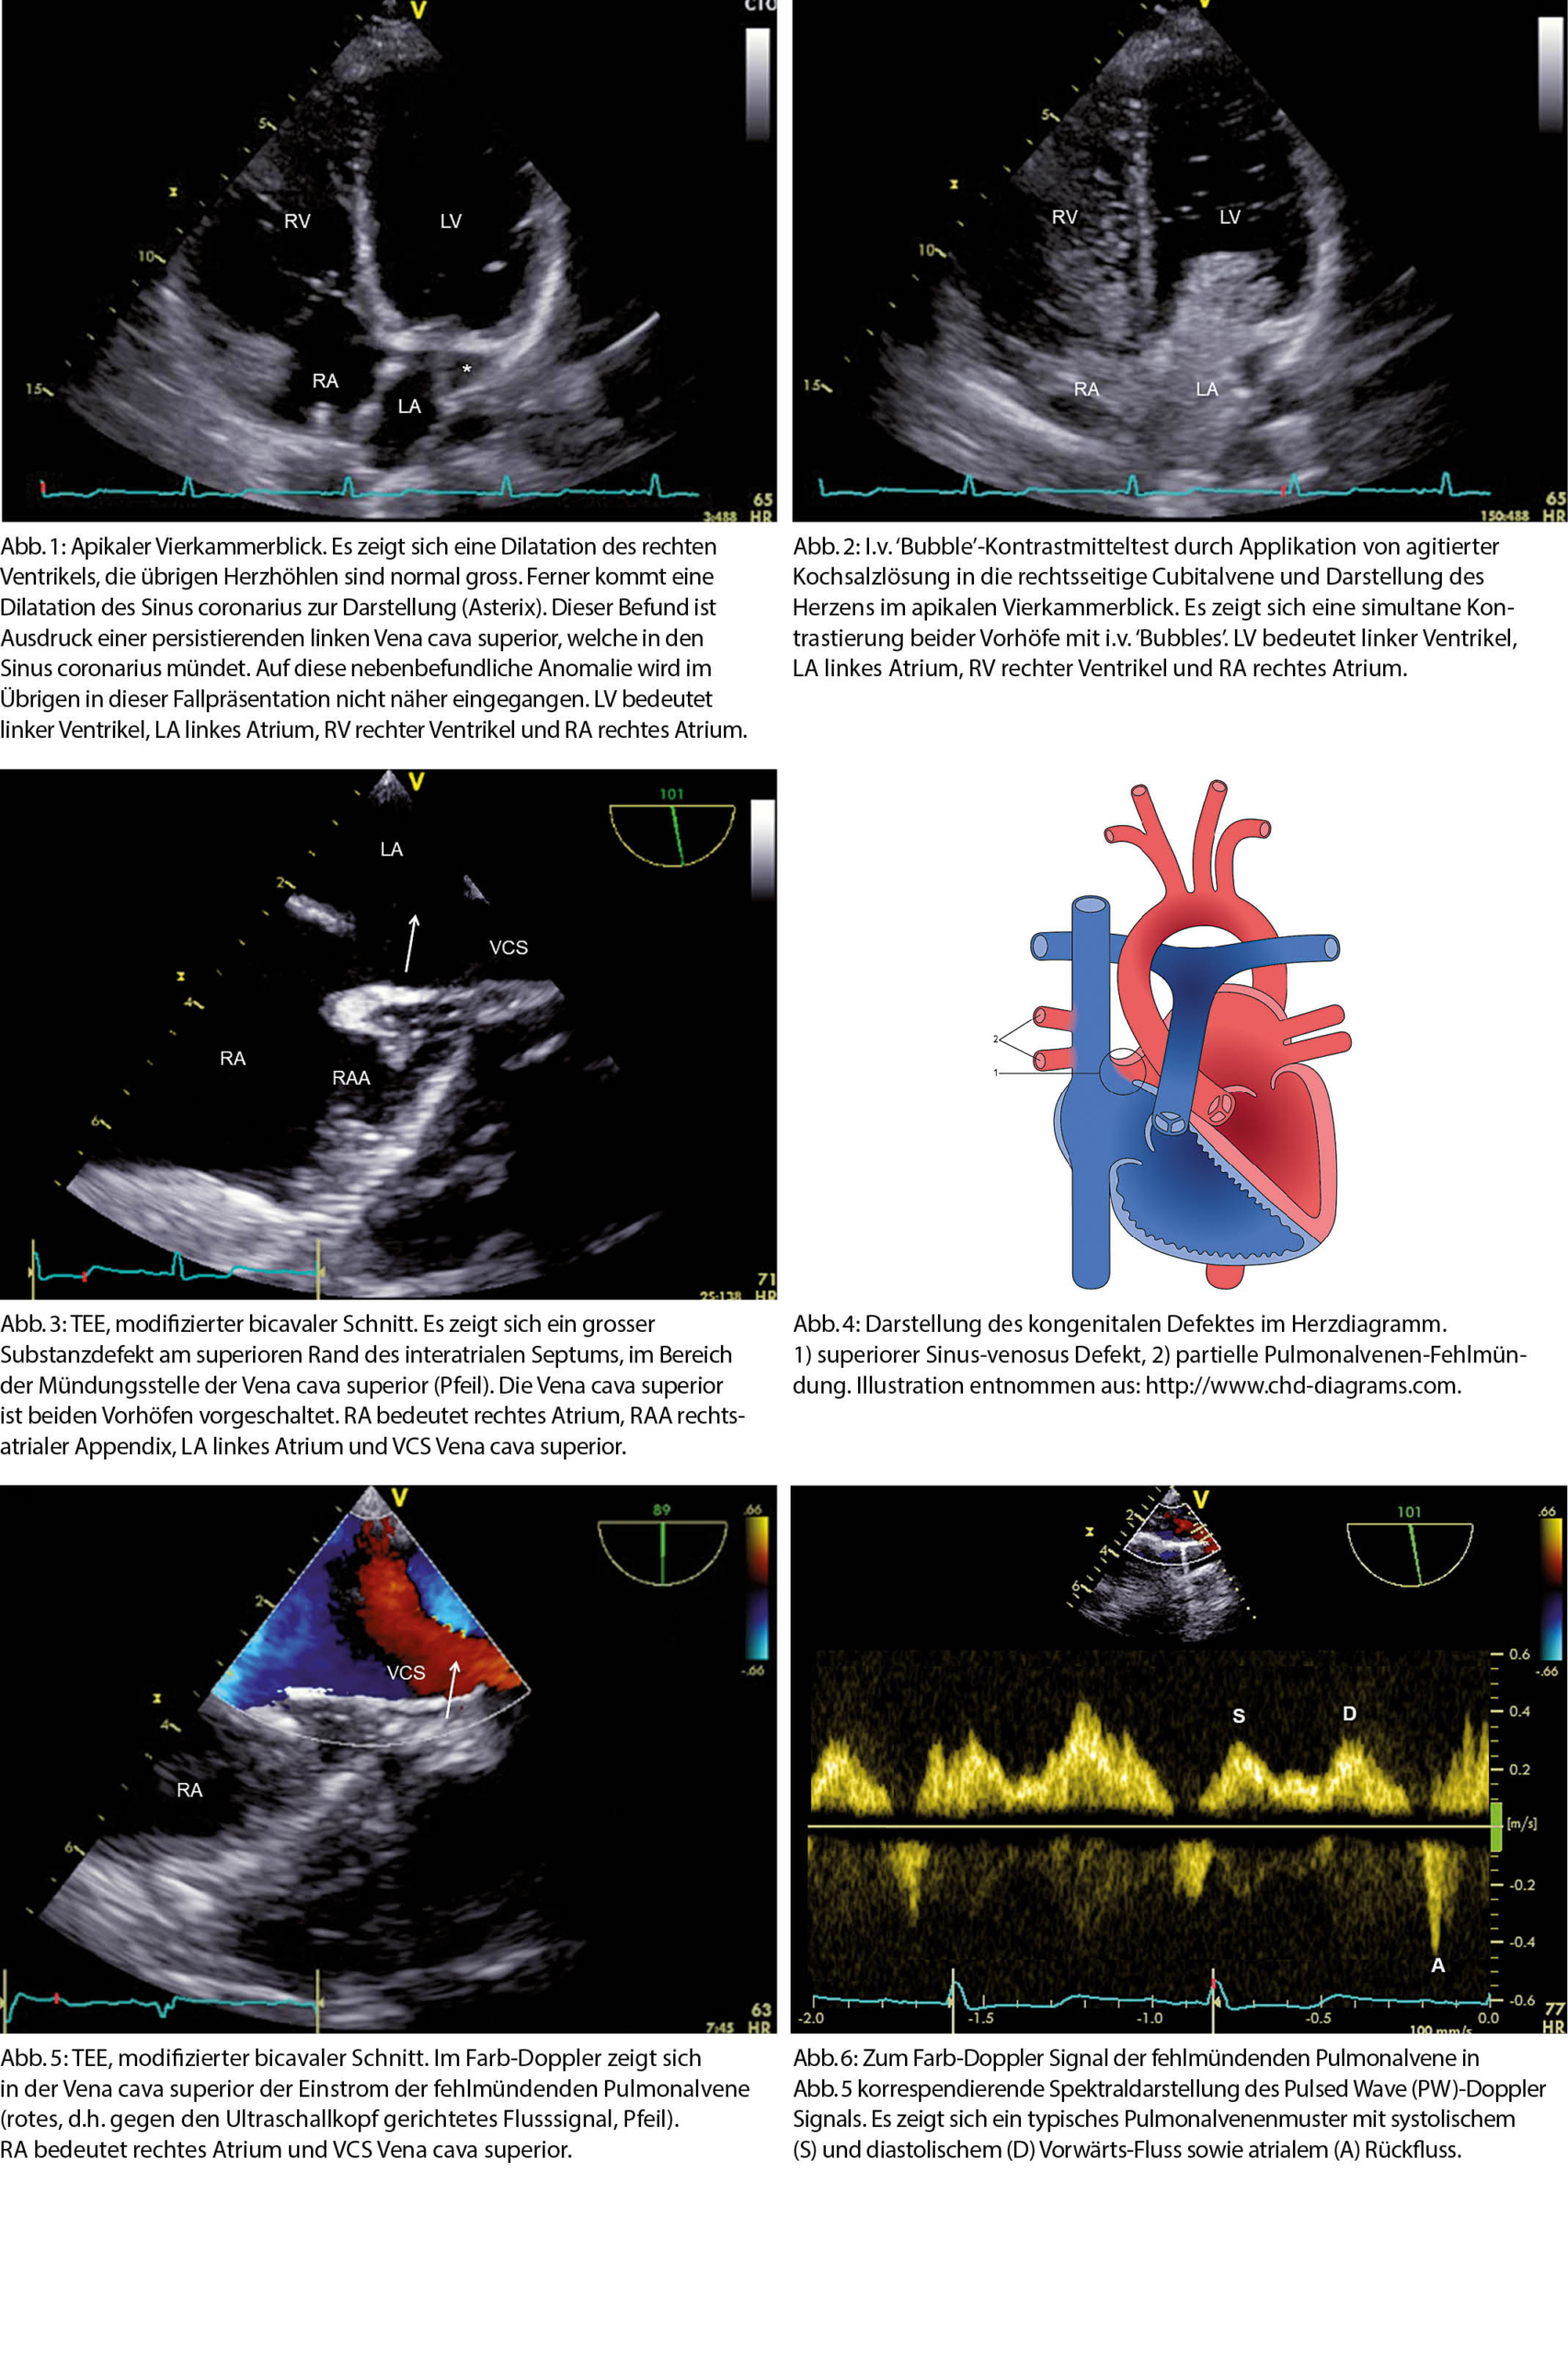

In der transthorakalen Echokardiographie drei Tage nach dem Myokardinfarkt zeigte sich ein normal dimensionierter linker Ventrikel mit einer LVEF von biplan 65%. Im Gegensatz zum linken Ventrikel war der rechte Ventrikel dilatiert (Abb. 1), was bei normal funktionierenden rechtsseitigen Herzklappen den Verdacht auf das Vorhandensein eines Shunt-Vitiums nahelegte. Es wurde daher ein intravenöser (i.v.) ‘Bubble’-Test mit agitierter Kochsalz-Lösung durchgeführt. Nach der Injektion des Kontrastmittels von der rechtsseitigen Cubitalvene kam es zur gleichzeitigen Kontrastierung beider Vorhöfe (Abb. 2). Dieser Befund ist praktisch diagnostisch für das Vorhandensein eines oberen Sinus-venosus Defektes (1). Dieser liess sich in der transösophagealen Echokardiographie (TEE) in einer modifizierten bicavalen View gut darstellen (Abb. 3). Typischerweise findet sich dabei ein grösserer Substanzdefekt am superioren Rand des interatrialen Septums, im Bereich der Mündungsstelle der Vena cava superior. Diese ist dabei beiden Vorhöfen vorgeschaltet (2), was die simultane Kontrastierung der Vorhöfe im ‘Bubble’-Test erklärt.

Der obere Sinus-venosus Defekt findet sich bei etwa 5-10% aller Patienten mit einem Vorhofseptumdefekt (3). Eine partielle oder vollständige Fehlmündung der rechtsseitigen Pulmonalvenen in die Vena cava superior ist bei diesem Defekt sehr häufig (Abb. 4) (3, 4). Auch bei unserer Patientin liess sich mittels Farb-Doppler (Abb. 5) und Pulsed-Wave (PW)-Doppler (Abb. 6) ein Pulmonalvenen-Einstrom in die Vena cava superior aufzeigen. Im Angio-CT zeigte sich, dass es sich um eine einzelne fehlmündende obere rechte Pulmonalvene handelte.